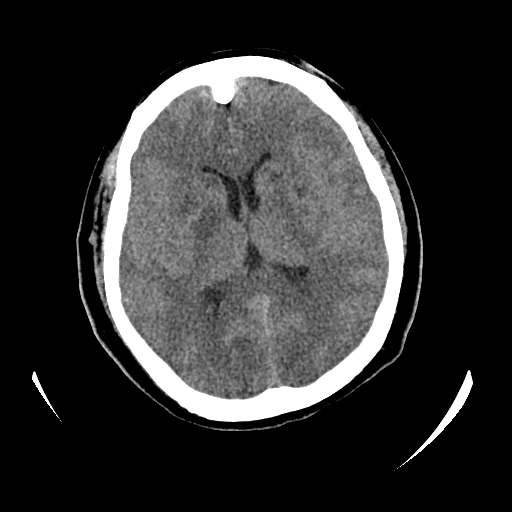

女,53岁,发现昏迷1天,血压不高,有精神病史。临床诊断:脑梗死?

ct诊断:1、双侧基底节区对称性脑梗塞。

2、双侧额叶、枕叶广泛密度减低,考虑缺血梗塞可能性大。

3、脑池小,脑沟浅,提示颅内高压。

测左枕叶白质ct值 约22hu 。请各位老师给出恬当诊断。

征象:病变呈对称性分布于双侧大脑半球,累及范围广泛,白质较灰质密度减低更为明显;脑沟变浅,脑池变窄;